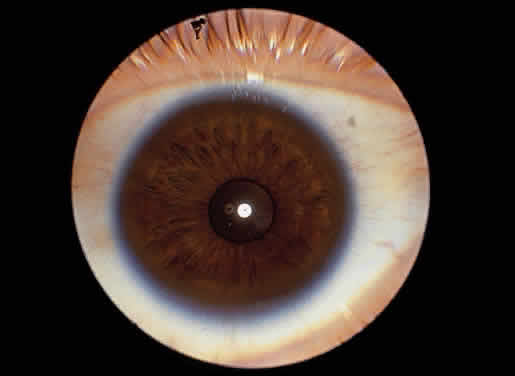

Corneal clouding was recognized early to be an important feature of this disorder, and classic clinical descriptions of the corneal changes are to be found in the older literature.8–12 Clouding of the cornea is usually evident by age 2 to 3 years, often by age 1 year; in some cases it is seen at birth.12,13 Photophobia is a common early symptom. With time there is progression from a generalized haziness or steamy appearance to a dense, milky ground-glass opacification (Fig. 2). On slit-lamp examination, one sees fine granular opacities in the corneal stroma, often increasing in density from the anterior stroma and subepithelial region to the posterior stromal layers.10–12

Corneal clouding is a prominent manifestation of the Scheie syndrome.18 Developing early in life, sometimes present at birth, the corneal clouding tends to worsen with age and may ultimately interfere with vision. The corneal involvement is diffuse but tends to be most dense peripherally. Clinically the hazy cornea may appear enlarged, edematous, and thickened, initially raising suspicion of glaucoma, particularly when telltale somatic signs of mucopolysaccharidosis are minimal.

Corneal clouding is a feature of Morquio syndrome,66 although some of the earlier literature would suggest otherwise.26 The corneal clouding in Morquio syndrome is relatively mild, having the appearance of a fine haze rather than the dense ground-glass opacification common to Hurler syndrome. The changes may not become clinically evident to the unaided eye for several years, often not before age 10 years. In the early stages the corneal involvement may be overlooked unless careful slit-lamp examination is performed. The biomicroscopic appearance is that of diffuse involvement of the stroma with punctate or granular opacities but usually sparing of the epithelium, Bowman's layer, and endothelium. Depending on the density of the corneal haze, there may be some impairment of vision but usually not of a severe degree. Corneal clouding is seen in MPS IV-B as well as in MPS IV-A.67,68

The principal ophthalmologic manifestation of MPS VI is progressive corneal clouding, usually evident within the first few years of life. The appearance is that of ground-glass haze distributed diffusely throughout the stroma, sometimes denser peripherally, and usually of sufficient degree to be seen grossly.75,76 In addition to the stromal opacities, some epithelial and endothelial changes may be seen on slit-lamp examination.76 Corneal opacities have been documented in the mild variant of MPS VI as well in the severe form.77 A decrease in corneal clouding after bone marrow transplantation has been noted.78 In what appears to be the first reported histopathologic study of the eye in Maroteaux-Lamy syndrome, Kenyon and coworkers in 1972 described changes typical of mucopolysaccharidosis.76 On light microscopy they found cytoplasmic vacuolization of corneal epithelium, interruption of Bowman's layer with accumulation of foamy histiocytes, swelling of keratocytes with foamy cytoplasm and separation of stromal lamellae, some cytoplasmic vacuolization of corneal endothelium, but essentially no alteration of Descemet's membrane. Other findings included thickening of sclera with vacuolated cells between the fibers, vacuolated cells in the trabecular meshwork, ballooned histiocytes, vacuolated fibrocytes in connective tissue stroma of the ciliary body, involvement of the basal portion of nonpigmented ciliary epithelium, and some changes in the choroid. By histochemical techniques, they documented accumulation of acid mucopolysaccharide in the affected cells and tissues. The retina appeared normal except for the macular area, where reduction of the ganglion cell population and thinning of the nerve fiber layer were noted. The optic nerve showed atrophy and secondary gliosis. Electron microscopy confirmed the presence of single membrane-limited vacuoles containing predominantly fibrillogranular material, some containing polymorphous material and membranous lamellae, in the cornea, sclera, trabecular meshwork, and uveal tract, but not in the retina.